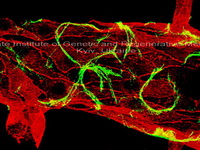

Regenerative potential of neural stem cells

at experimental ischemic stroke in vivo

The Laboratory which is engaged in study of the structural and ultrastructural characteristics of neuron, glial and neural stem/progenitor cells in normal and pathological conditions; cellular and molecular mechanisms underlying plasticity of nervous system growth, development, learning and memory.

In studies conducted in the Laboratory, widely use methods of cell culture, light and electron microscopy, histochemistry, immunohistochemistry, quantitative ultrastructural analysis, computer image analysis and morphometry, mathematic modeling.

The Laboratory has light microscope XSP-139A-TP with digital camera Canon Power Shot G-6; confocal scanning microscope Olympus FV1000-BX61WI, transmission electron microscope JEM-100CX and equipment necessary for cell culture and experiments in vivo and in vitro.